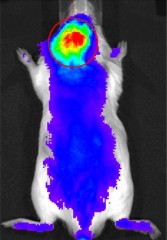

A nanocarrier tagged with a near infrared fluorescent marker gravitated toward inflammatory cells that had been injected into the area over the scalp. |

Performing an entire joint replacement surgery would be complicated in a mouse, so the researchers took a shortcut to mimic what happens in a human joint replacement that fails. The researchers injected wear particles from a human joint replacement into mice; specifically, they injected the particles into the area over the scalp. This generated an inflammatory reaction similar to what would be seen in humans in a joint replacement that was deteriorating. They then injected the nanocarrier tagged with a near infrared fluorescent marker into the bloodstream and showed that these nanocarriers gravitated toward the inflammatory cells. Autopsies of the mice verified this finding. Investigators then showed that the nanocarrier system could deliver dexamethasone, an anti-inflammatory drug, directly to the site of inflammation where it effectively inhibited inflammation and prevented osteolysis.